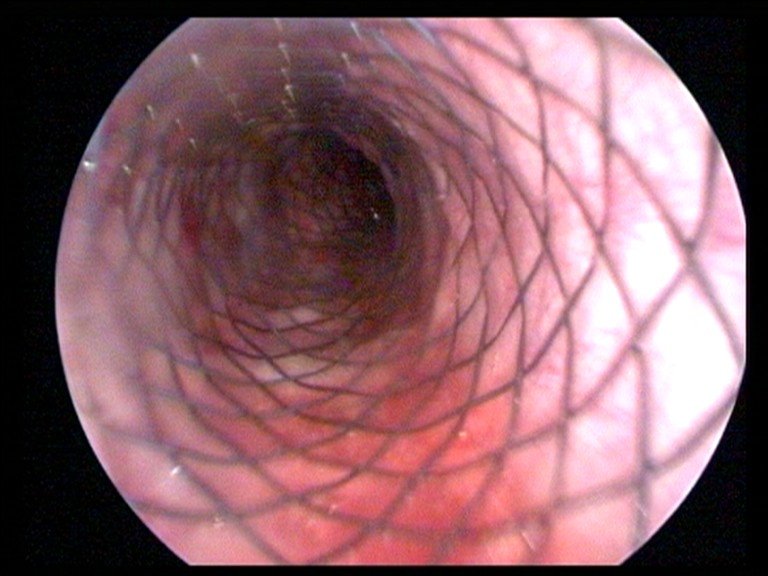

При спорном диагнозе обязательным условием является проведение эндоскопического исследования верхних отделов дыхательных путей. Оно выполняется под седацией и дает возможность объективно оценить состояние гортани, трахеи, магистральных бронхов.

Эндоскопическая картина коллапса трахеи